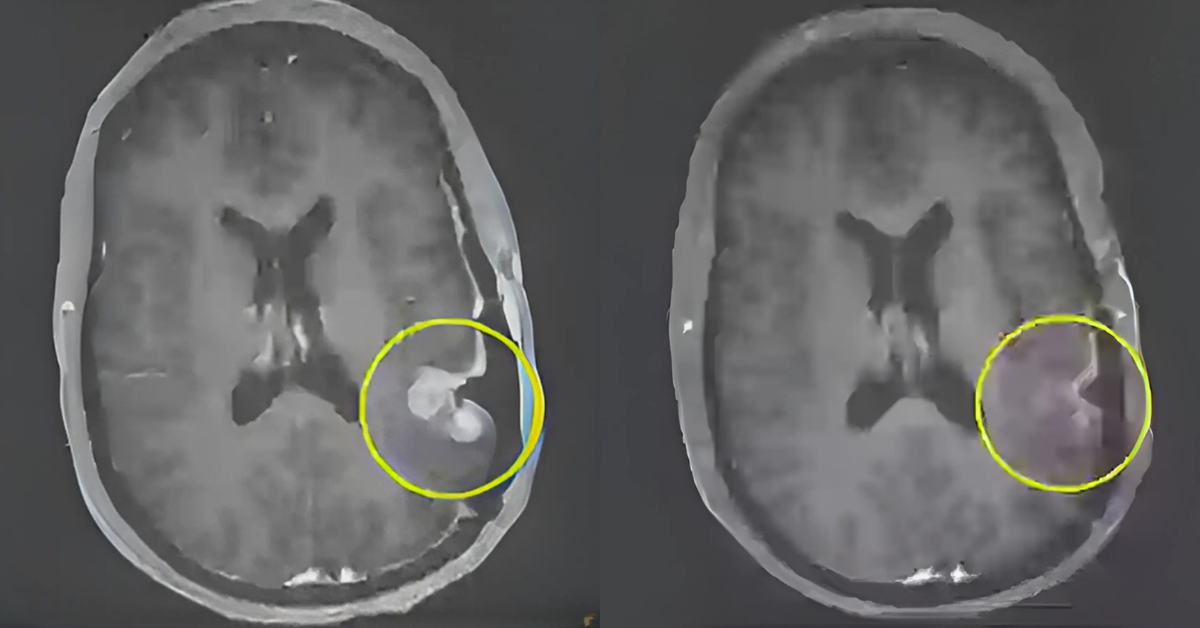

Os resultados surpreenderam até mesmo os próprios cientistas. Um dos pacientes apresentou uma redução de 18,5 % no tamanho do tumor em apenas dois dias, chegando a 60,7 % em 69 dias. Outro paciente mostrou regressão rápida, embora os dados detalhados não tenham sido divulgados. Mas o caso mais impressionante foi o de uma mulher de 57 anos, cujo tumor praticamente desapareceu em apenas cinco dias após uma única infusão. As imagens de ressonância magnética mostraram uma resposta quase completa, um feito inédito para esse tipo de tumor.